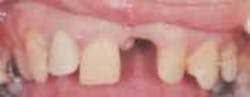

As dentists, we all wish for motivated patients to walk through our doors every day, ready to begin dental work. On one particular day, Mark, a 48-year-old patient, did just that. Mark was missing Tooth No. 9 and had an esthetic reason for seeking care (Figure 1). Besides the missing anterior tooth, what he didn't realize was how much his periodontal health had deteriorated.

Mark's primary motivation for treatment was to improve his smile for his upcoming wedding. My concern was not only to satisfy his immediate goal, but to improve his periodontal health, offer tissue-compatible restorative options, and finally, educate him about his treatment needs, thus maintaining his smile and periodontal health for years to come.